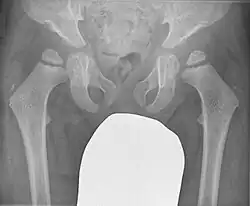

Die Spondyloepiphysäre Dysplasie (SED) umfasst eine Gruppe von seltenen oder sehr seltenen, zu den Chondrodysplasien zählenden Skelettdysplasien mit Veränderungen der Wirbelkörper und der Epiphyse der langen Röhrenknochen. Hauptmerkmal ist der dysproportionale Kleinwuchs.[1][2]

Rö Beckenübersicht, 3 J alt, männlich mit SED

Der klinische Verdacht aufgrund des dysproportionalen Kleinwuchses mit kurzem Rumpf und gelenknahen Verformungen der Extremitäten wird durch die Veränderungen im Röntgenbild bestätigt: